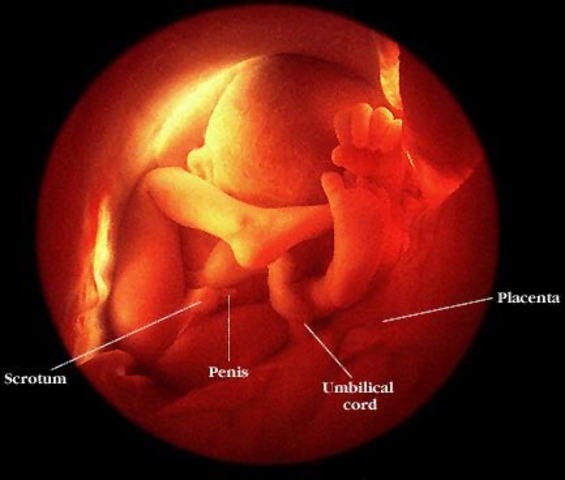

• week 15 of the fetal development

week 15 of the fetal development

All major organ systems are developed and are functioning. Fine hair called lanugo develops on the head. Genitalls are reconizable. Bones become harder. Fetus starts moving around.